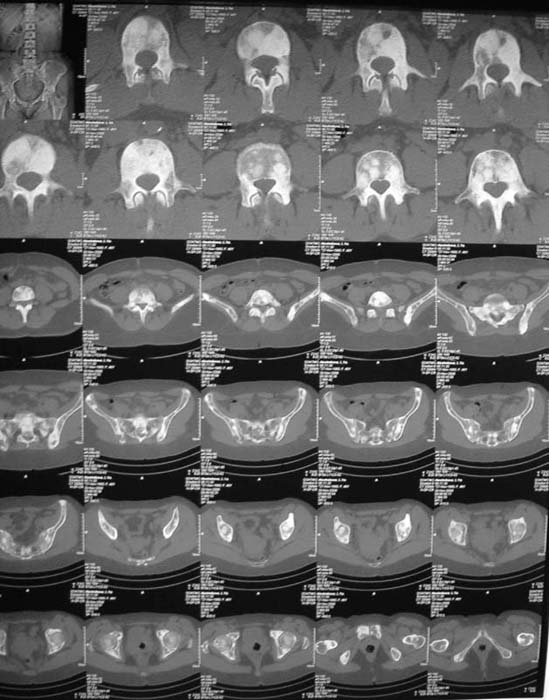

Диагноз, исходя из сцинтиграфии, предположительно метастазирование без определения первичного очага. Я сделал бы КТ органов и костей таза. Следующим шагом желательно взять биопсию, возможно из крыла таза (будет проще) после четкой визуализации очагов на КТ...